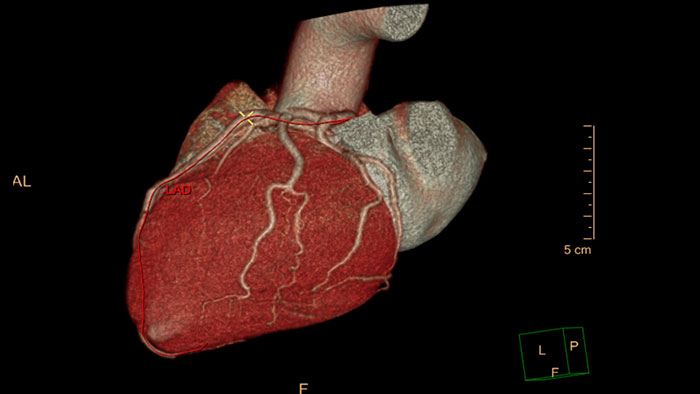

Emory Cardiac Toolbox (ECTb) HeartFusion

Emory Cardiac Toolbox (ECTb) HeartFusion*

Evaluate fused coronary anatomy

Emory Cardiac Toolbox (ECTb) HeartFusion offers fusion of a patient’s coronary tree from cardiac CT angiography with MI perfusion images.

ectb heartfusion thumbnail

Benefits

• Helps correlate stenosis with perfusion defects and identify muscle mass at risk.

*Emory Cardiac Toolbox, ECTb, HeartFusion, and SyncTool are registered trademarks of Emory University.